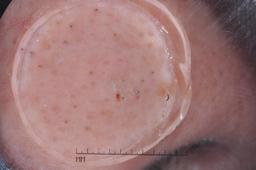

ISIC-DICM-17K (ISIC Dermoscopic Images and Clinical Metadata 17K) is a curated and balanced dataset derived from the International Skin Imaging Collaboration (ISIC) Archive Gallery. It comprises 17,060 dermoscopic images and clinical metadata (8,530 melanoma and 8,530 non-melanoma classes).

For more details, please follow the project’s GitHub repository: https://github.com/mmu-dermatology-research/isic-dicm-17k

This dataset was used in this study and benchmark to explore the effectiveness of multimodal learning for skin lesion classification:

S. Ahammed, X. Cui, W. Lu and M. H. Yap, "Skin Lesion Classification using Dermoscopic Images and Clinical Metadata: Insights from Multimodal Models," 2025 IEEE/CVF Conference on Computer Vision and Pattern Recognition Workshops (CVPRW), Nashville, TN, USA, 2025, pp. 222-230, DOI: 10.1109/CVPRW67362.2025.00027